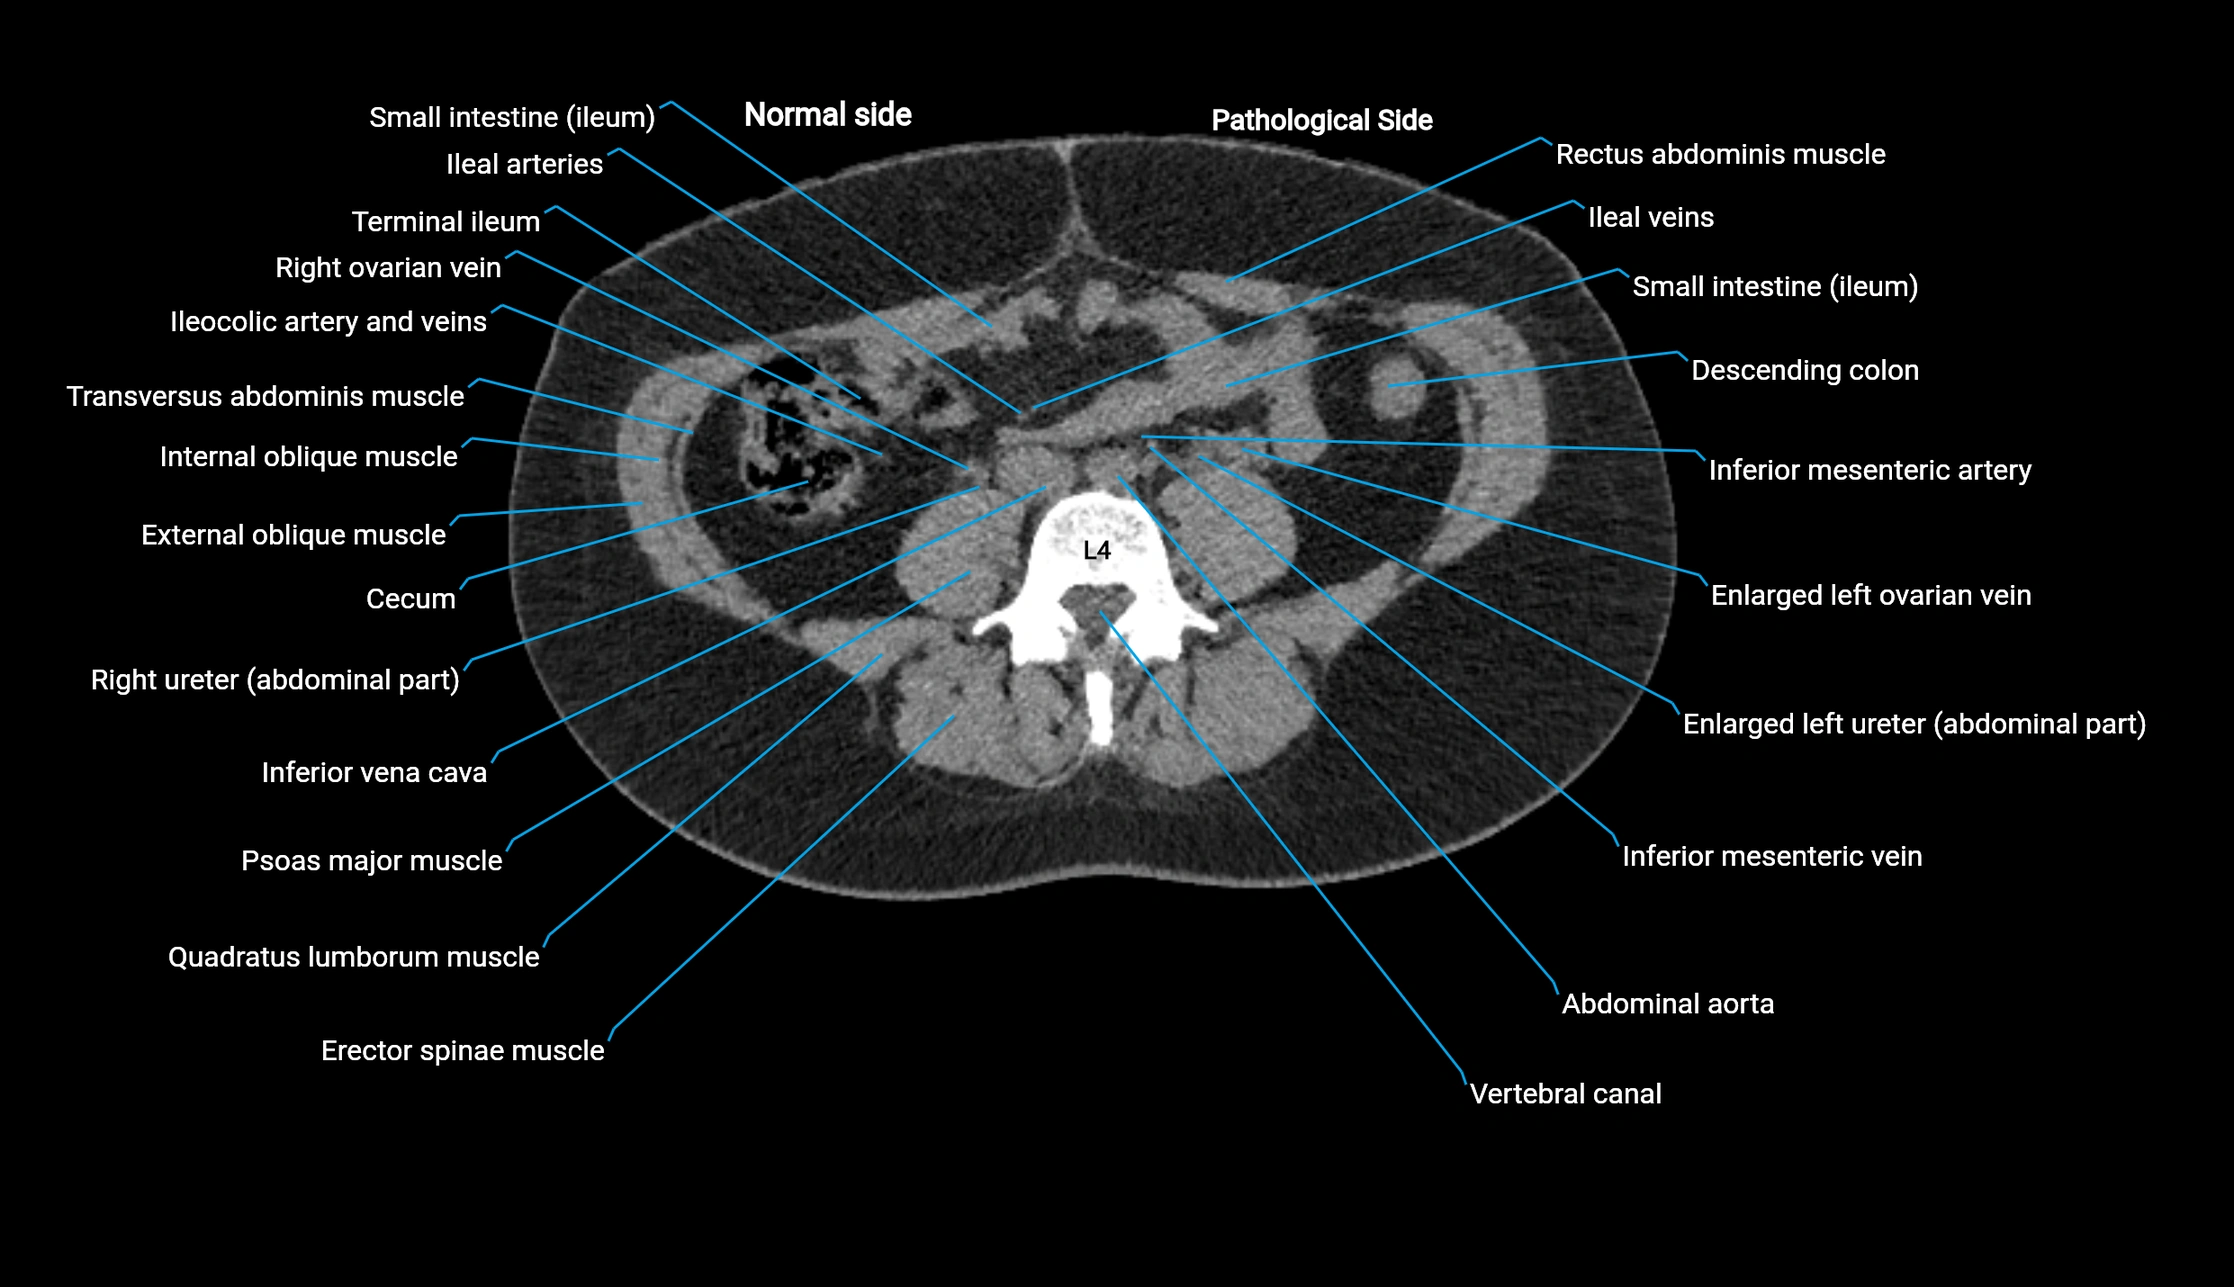

CT image

image